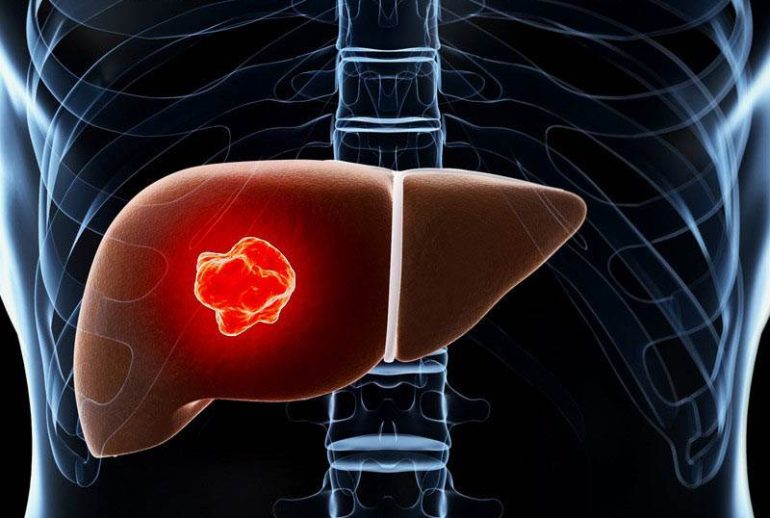

برداشتن کبد یا هپاتکتومی، یک عمل جراحی است که طی آن تمام یا بخشی از کبد برداشته میشود. این عمل معمولاً در موارد ابتلا به سرطان کبد، آسیبهای شدید ناشی از تصادف، یا بیماریهای مزمن کبدی که منجر به نارسایی کبد شدهاند، انجام میشود.

- سرطان کبد: یکی از شایعترین دلایل برداشتن کبد، ابتلا به سرطان اولیه کبد یا متاستاز سرطانهای دیگر به کبد است.